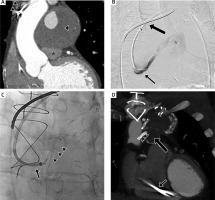

A patient with an implantable cardioverter-defibrillator and a past history of multiple coronary arterial bypass grafting (Ao-DIAG-LAD, Ao-RCA, SVG-OM, LITA-LAD) and angioplasty of the Ao-DIAG-LAD graft was admitted due to worsening dyspnea. Coronary computed tomography (CT) angiography revealed the presence of a partially thrombosed SVG-OM bypass graft aneurysm, measuring 73 × 66 × 61 mm and causing pulmonary trunk narrowing to 11 mm in the anteroposterior (AP) view (Figure 1 A); another fully thrombosed, smaller aneurysm was visible at the occluded distal segment of the graft. A third aneurysm was detected at the proximal Ao-DIAG-LAD graft; full patency of the previously stented graft with no filling of the aneurysm was observed. Although patients with mechanical complications of coronary graft aneurysms, e.g. compression of adjacent vascular structures, are routinely treated by classic cardiac surgery [1], it was decided to refer our patient for less invasive endovascular exclusion of the partially filling SVG-OM graft aneurysm due to extensive post-operative retrosternal fibrosis and signs of cardiac insufficiency (ejection fraction (EF) = 28%). Based on distal graft impatency and severe compression symptoms, occlusion of the afferent graft segment was chosen as the best treatment option in order to promote aneurysm shrinkage. Deployment of a vascular plug seemed to be the method of choice due to a short (< 15 mm) landing zone, rapid, single-device vessel occlusion and no additional mass to be left within the aneurysm sac. Amplatzer Vascular Plug 4 (AVP4 – St. Jude Medical, MN, USA) 6 × 11 mm was selected as the most appropriate device. Consecutive stages of the embolization procedure performed under local anesthesia are presented in Figures 1 B and C. Control angiography confirmed proper positioning of the occluder and lack of contrast filling in the bypass graft and aneurysm sac.

Figure 1

Giant aneurysm of the saphenous vein graft-obtuse marginal branch (SVG-OM) venous bypass graft. A – Coronal reconstruction of the coronary angio-computed tomography (angio-CT) depicting giant, partially thrombosed aneurysm of the SVG-OM bypass graft (arrow) compressing the pulmonary trunk (asterisk). Electrode of the implantable cardioverter-defibrillator directing to the right ventricle visible as well (arrowheads). B – Pre-procedural angiogram of the SVG-OM bypass graft depicting aneurysm filling with contrast medium (asterisk); a 6 Fr 90 cm-long vascular sheath (Flexor, Cook Medical, IN, USA) was placed at the level of the ascending aorta (thick arrow) through a right femoral access, followed by coaxial, selective positioning of the 5 Fr MPA (Cook Medical, IN, USA) diagnostic catheter in the proximal SVG-OM bypass (arrow). C – Preceded by administration of 3000 IU heparin i.v., a 6 mm Amplatzer Vascular Plug (AVP) 4 (arrowheads) was then deployed with a slight oversizing into the 5 mm target graft resulting in complete aneurysm exclusion from the circulation; just before AVP deployment the 6 Fr vascular sheath was advanced to the proximal SVG-OM bypass to provide system stability (arrow). The arterial puncture site was closed by StarClose (Abbott Vascular, IL, USA). The patient received low molecular weight heparin (LMWH) s.c. daily for routine postoperative thrombosis prophylaxis, and after discharge was prescribed with optimal medical treatment (acetylsalicylic acid (ASA) 75 mg, statin, angiotensin-converting-enzyme inhibitor (ACEI) and angiotensin II receptor blocker (ARB)) as standard of care, not to impede the effects of AVP with additional antithrombotic agents. D – Control coronary angio-CT at 12 months depicts AVP 4 (asterisk) successfully implanted to the proximal SVG-OM bypass graft, with no residual flow through the aneurysm sac. Fully thrombosed aneurysm of the aorta-diagonal branch-left anterior descending artery (Ao-DIAG-LAD) bypass (thick arrow) with stent deployed within patent graft vessel (arrowheads) is visible as well. Electrode of the implantable cardioverter-defibrillator directing to the right ventricle visible as previously (arrow). Pulmonary trunk decompression is also visible

Coronary CT angiograms obtained at 3 and 12 months (Figure 1 D) follow-up confirmed effective occlusion of the bypass graft with complete thrombosis of the aneurysm sac. Aneurysm sac shrinkage to 67 × 63 × 58 mm and 60 × 62 × 51 mm was observed at 3 and 12 months follow-up, respectively. This was accompanied by pulmonary trunk decompression to 19 mm in the AP dimension at the 12-month follow-up, and symptom resolution.